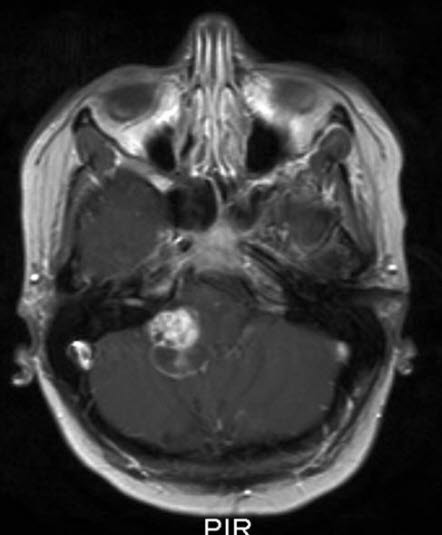

Pilocytisk astrocytom, aksialt snitt

Pilocytisk astrocytom WHO grad I

Gjengitt med tillatelse av Radiologisk avdeling, Universitetssykehuset Nord-Norge